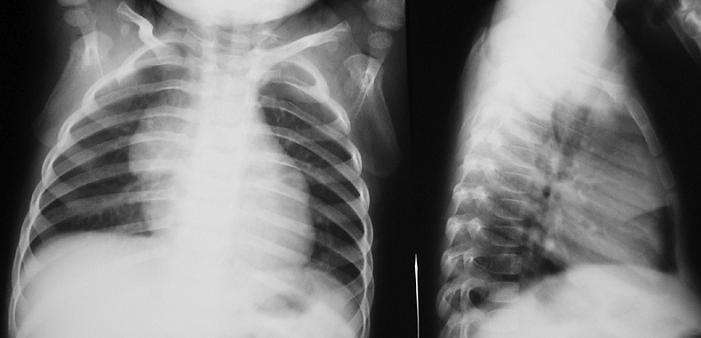

Тимомегалия: что это такое и как проявляется